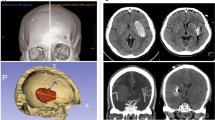

Demographic and clinical variables were collected, including sex, age, systolic and diastolic blood pressure upon emergency room admission, history of diabetes, and prior use of anticoagulant or antiplatelet medications. Additionally, preoperative Glasgow Coma Scale (GCS) scores and onset-to-surgery time were recorded. Laboratory parameters retrieved from the hospital database included blood type, hemoglobin levels, neutrophil and lymphocyte counts, platelet count, prothrombin time (PT), and activated partial thromboplastin time (APTT). Hematoma volume and surface area were quantified using 3D Slicer (version 5.6.2; Slicer Community, Brigham and Women’s Hospital, Boston, MA, USA) based on the final preoperative CT scan, with intraventricular hemorrhage excluded from the calculation. Hematomas were manually segmented on a slice-by-slice basis using a threshold range of 50–100 Hounsfield units, followed by the generation of a three-dimensional model, enabling precise measurement of hematoma volume and surface area. Similarly, residual hematoma volume was assessed from the immediate postoperative CT (Fig. 1). Hematoma evacuation rate is defined as (preoperative hemorrhage volume - residual hematoma volume)/preoperative hemorrhage volume*100%. Surgical time is defined as the duration from skin incision to wound closure. If additional procedures, such as external ventricular drainage or other surgeries, were performed intraoperatively, the time required for these additional procedures was not included in the surgical time calculation. Rebleeding was defined as a postoperative hematoma volume greater than the preoperative volume, a postoperative hematoma volume less than the preoperative volume but with a difference of less than 5 mL, or a gradual increase in postoperative hematoma volume by 10 mL. Additionally, we distinguished residual hematoma by reviewing the surgeons’ operative reports (regarding intraoperative hematoma evacuation) and assessing hematoma morphology on pre- and postoperative CT scans10. Intracranial infection was diagnosed based on the following criteria: (1) Clinical symptoms such as postoperative fever, headache, or neck stiffness. (2) Abnormal cerebrospinal fluid (CSF) findings: WBC > 10 × 10⁶/L, glucose < 2.25 mmol/L, chloride < 120 mmol/L, and protein > 0.45 g/L. (3) Positive CSF bacterial culture. Patients with criteria 3 could be diagnosed individually. Patients with negative CSF culture result but positive for the first 2 diagnostic criteria were also diagnosed as having intracranial infection11. Tracheostomy was performed in patients requiring prolonged mechanical ventilation (≥ 7 days), those with severe airway protection impairment due to decreased consciousness, or those with significant pulmonary complications12.